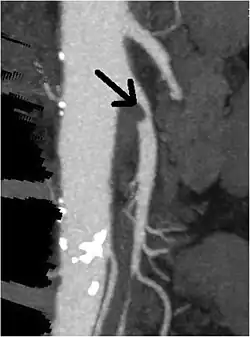

| CT angiogram demonstrating stenosis of the superior mesenteric artery. | |

Abdominal angina is diagnosed by identifying stenosis with imaging.[10] Since the symptoms of abdominal angina overlap with various other disorders, other causes of symptoms are ruled out as a part of the diagnostic process. Gastric ulcers, abdominal aortic aneurysms, and gastrointestinal cancers can have similar symptoms and can be ruled out by esophagogastroduodenoscopy, CT scans, or MR angiogram. Other differential diagnoses include GERD, dietary or food sensitivities, constipation, pancreatitis, abdominal abscess, appendicitis, irritable bowel syndrome, gastroenteritis, hepatitis, and inflammation of the gastrointestinal system.[11] Duplex ultrasound, MR angiography, angiography, and computed tomography angiography can be used to help confirm the diagnosis of abdominal angina.[3] Duplex ultrasound may be used to screen for abdominal angina but is not ideal for visualizing stenosis. Angiography, MR angiography, or CT angiography can be used to further visualize the celiac and mesenteric arteries.[12]